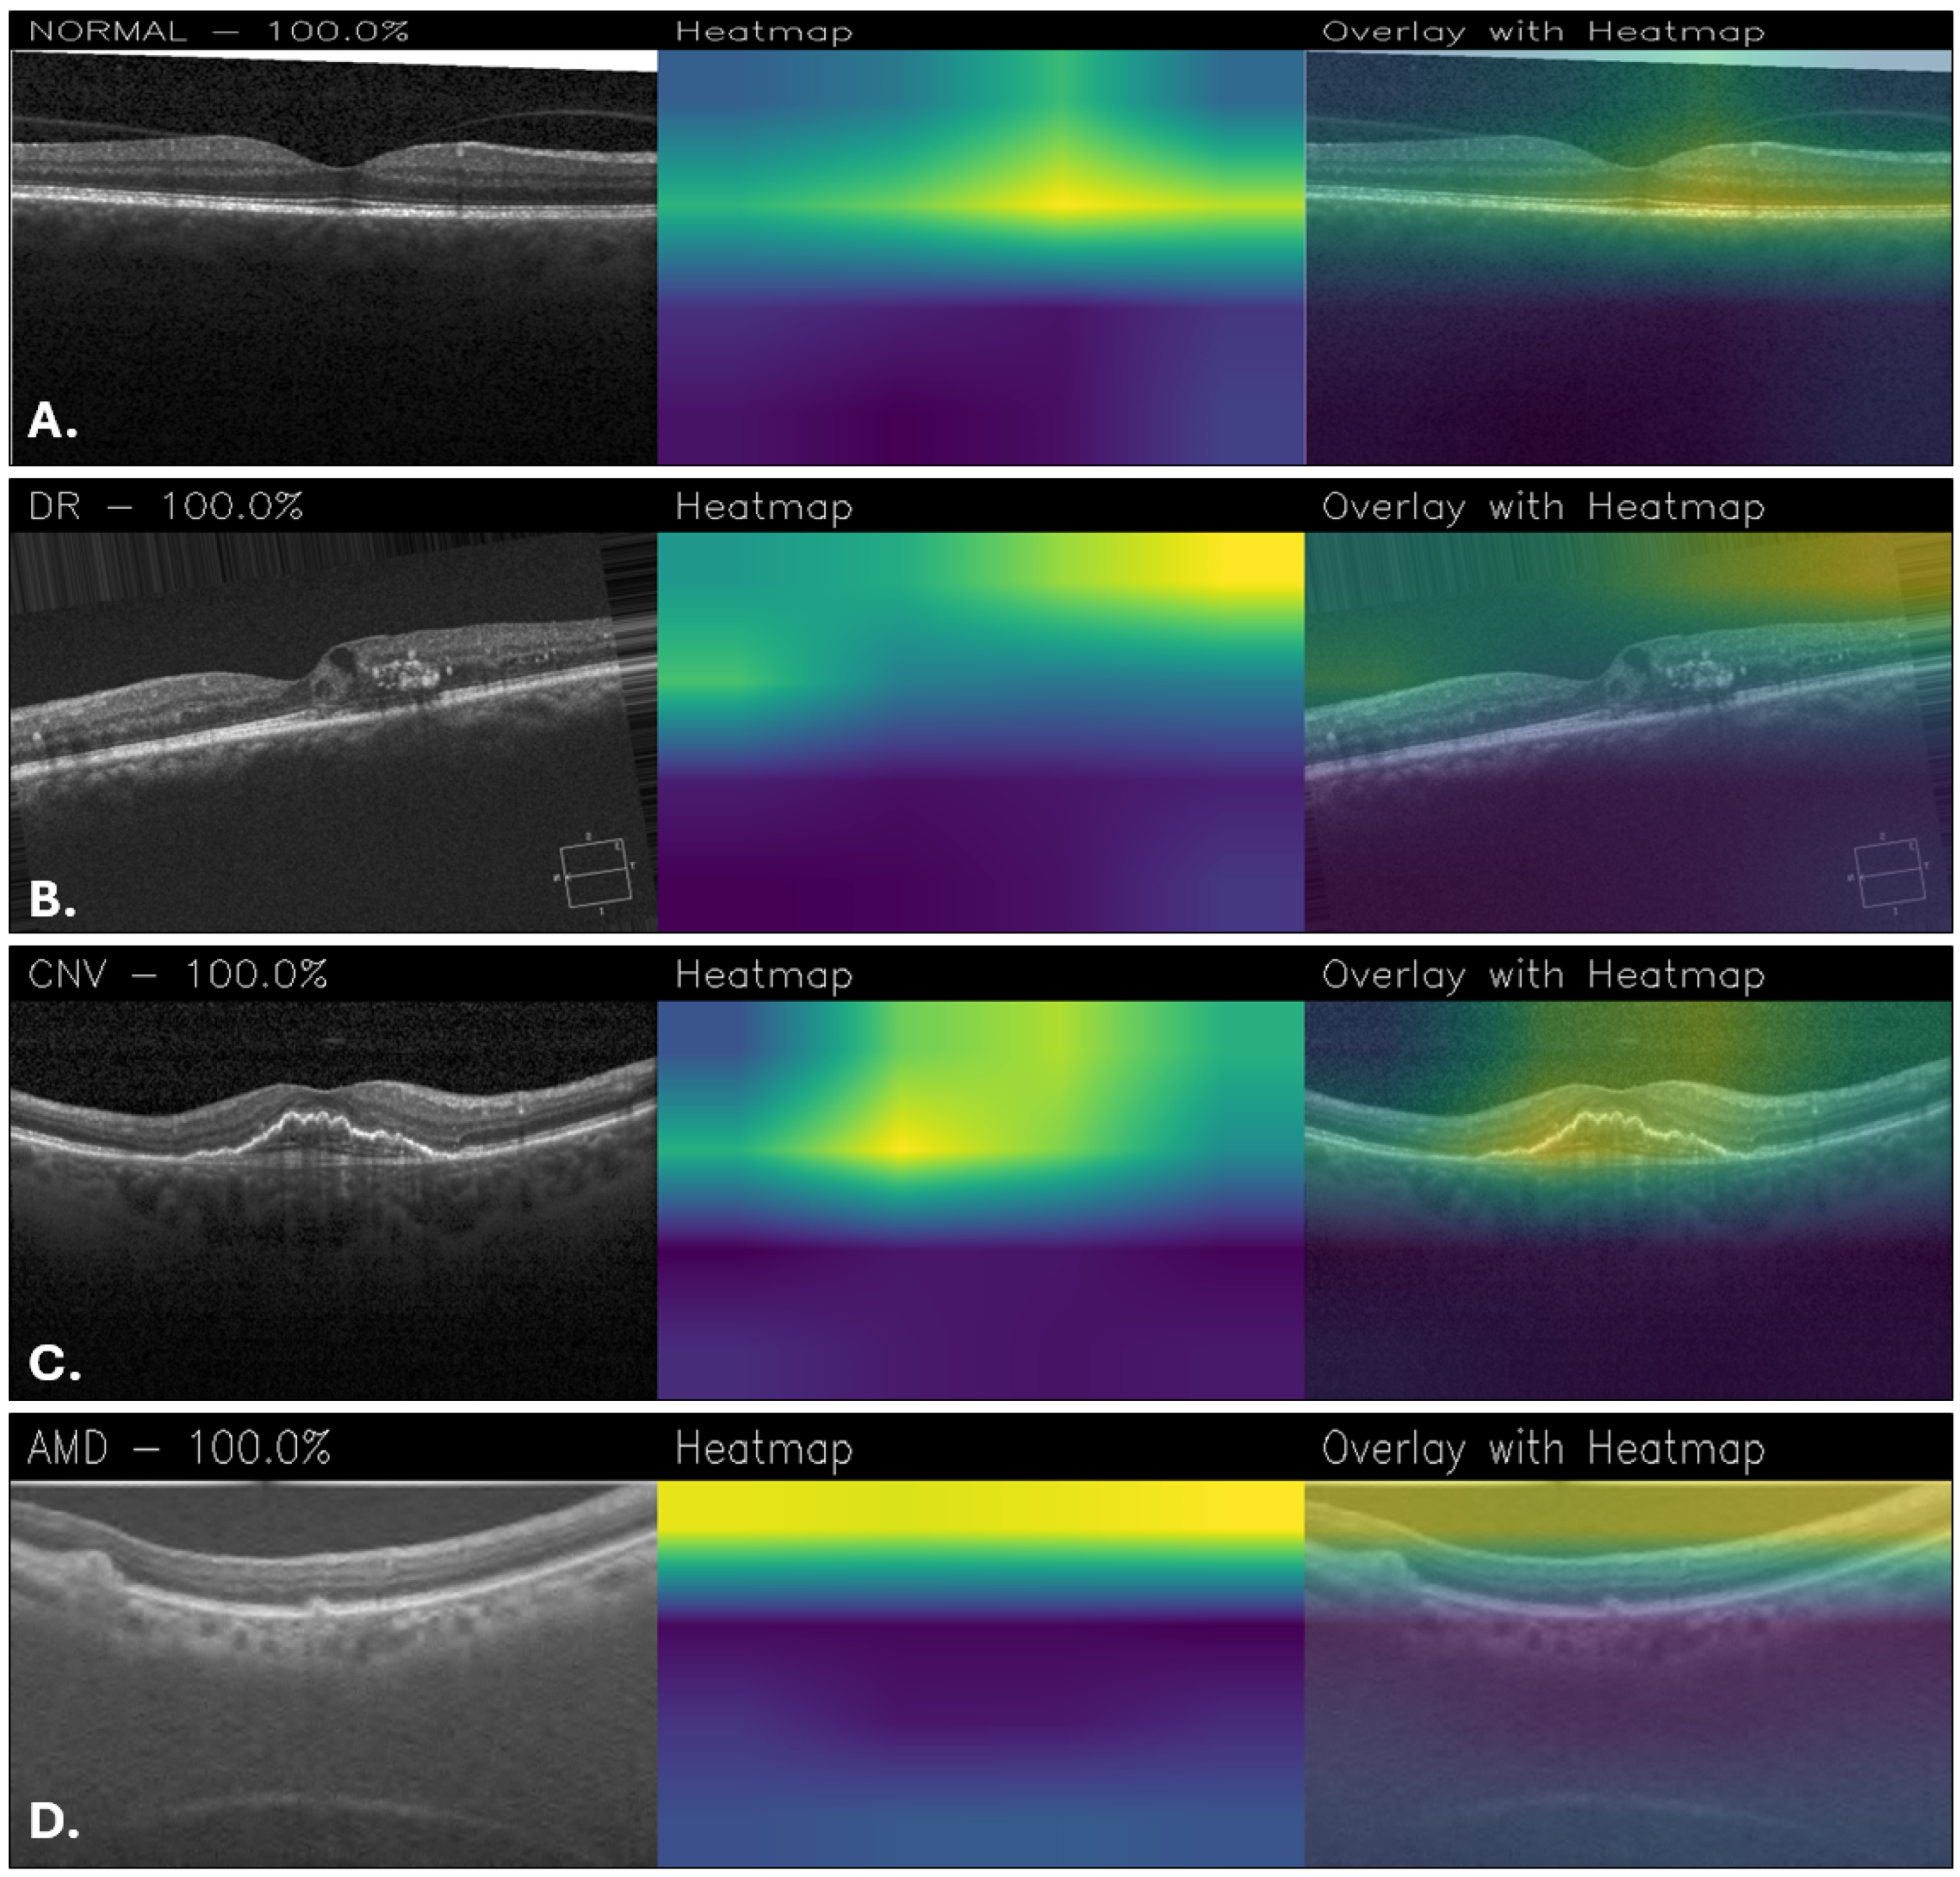

Figure 12 shows Grad-CAM visualizations of OCT images classified by the proposed MobileNetFT, highlighting the image regions most influential for the model’s decisions. For the healthy retina (Figure 12A), the activation is uniformly low across the retinal layers, with no focal areas of high importance, consistent with the absence of localized pathology. In DR (Figure 12B), the model emphasizes regions with hyperreflective lesions and retinal thickening, although some areas of the heatmap appear noisy. For CNV (Figure 12C), the central subretinal area corresponding to structural disruption shows the strongest activation. In AMD (Figure 12D), the heatmap highlights the outer retinal layers, particularly areas of drusen-like elevation and irregularity. However, the activations appear to be widely distributed, without focusing on specific details, as shown in Figure 12. This suggests that the model bases its decisions on general patterns rather than well-defined details, which may be beneficial to the robustness of the model but at the same time may limit its ability to recognize very fine details within the images.

Figure 12. Grad-CAM visualizations obtained with the MobileNetFT for healthy retina (A), DR (B), CNV (C), and AMD (D).